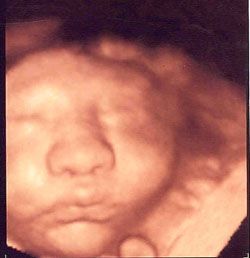

En Ultrasonido Diagnóstico de Hidalgo le brindamos una consulta profesional, realizando Ultrasonido de Embarazo desde su diagnóstico, acompañándole en el crecimiento y desarrollo de su bebe en cada semana de gestación, así como la revisión de los marcadores ultrasonográficos para la detección de alteraciones cromosómicas y estructura del feto. En el primero y Tercer trimestre del embarazo se realiza la revisión de las arterias uterinas para la prevención de la hipertensión de la mujer embarazada.

- Sexo del bebe y grabación del bebe

- Marcadores cromosómicos